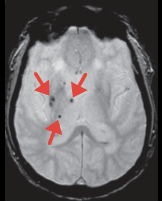

くも膜下出血の原因となる脳動脈瘤は、破裂前に発見することが可能です。小さな無症候性脳梗塞(いわゆる隠れ脳梗塞)や微小な脳内出血の痕跡も早期に発見することが可能ですので、今後の脳卒中予防の対策をとることが可能となります。

微小脳出血

(矢印)